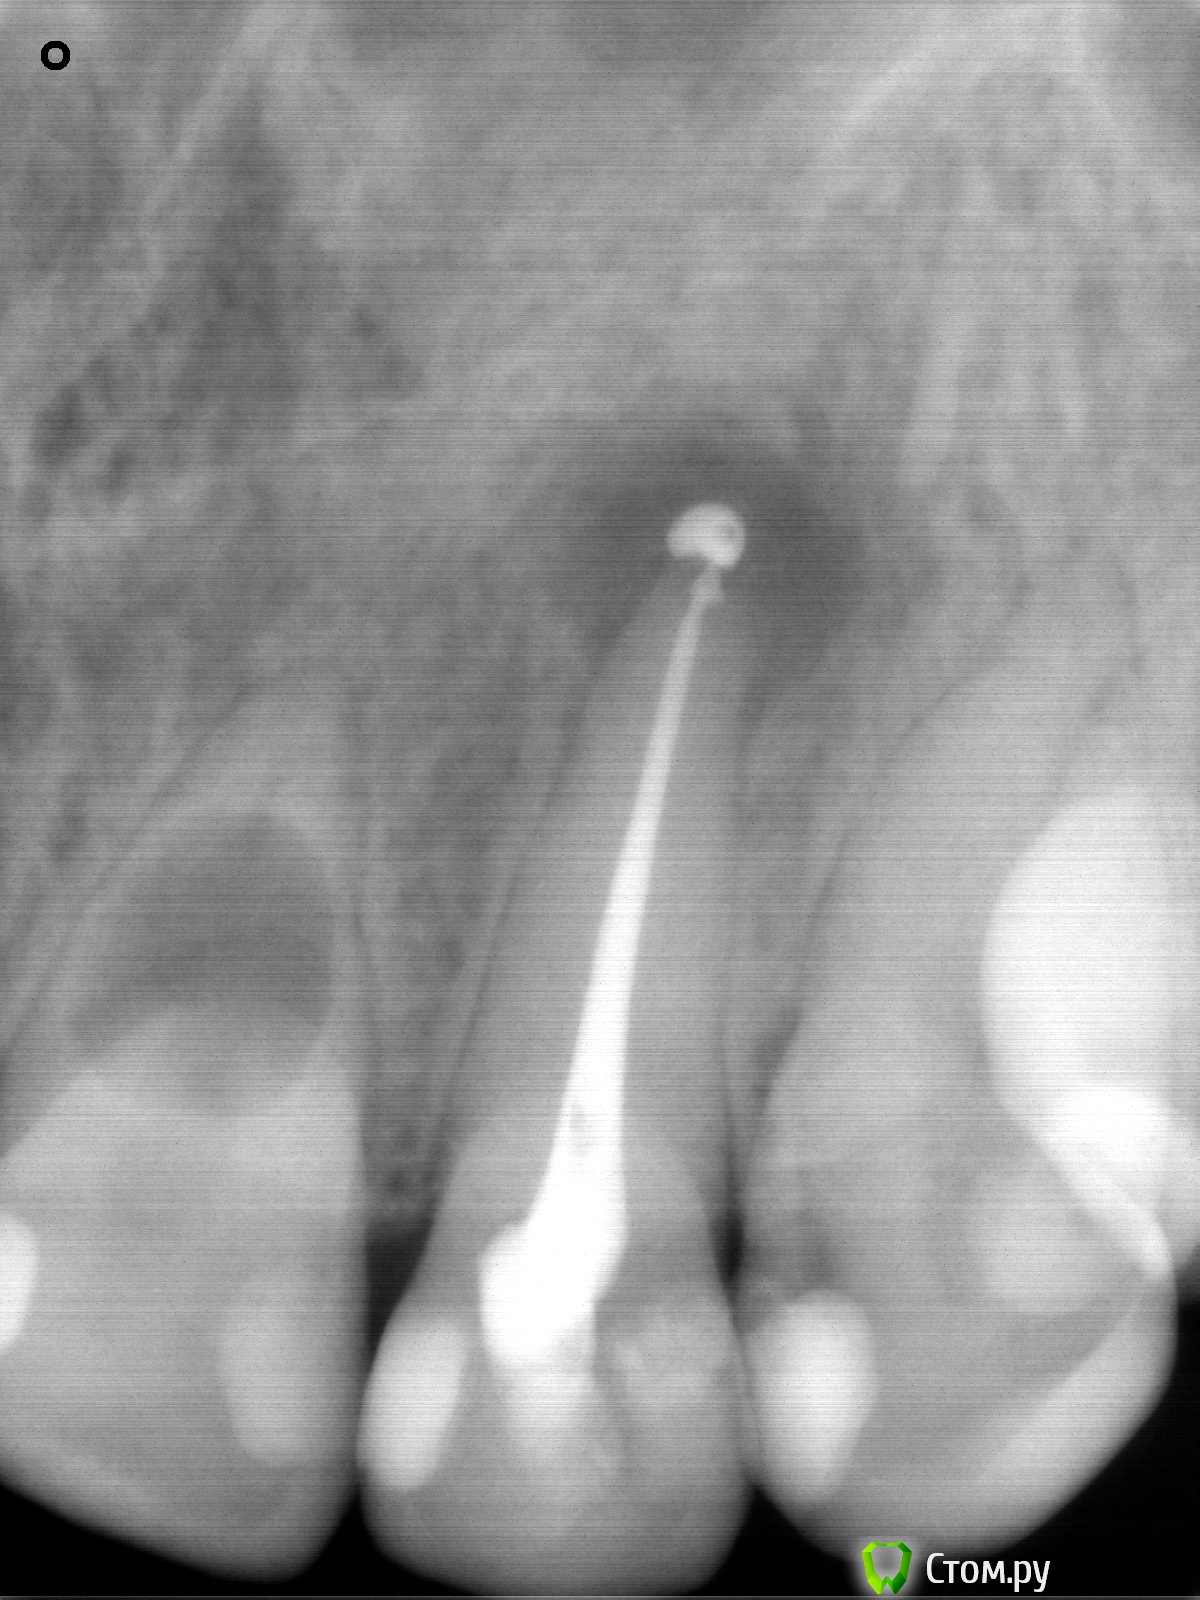

Yana5 Опубликовано 27 января, 2014 Автор Поделиться Опубликовано 27 января, 2014 пытаюсь сделать скриншоты, к сожалению, у меня пока не получается сделать срез 21 зуба. Возможно, будет информативным прицельный снимок, который мне сделали сегодня на 21 и 22? P.S. корректно ли, по Вашему мнению, запломбирован канал 22го? Ссылка на комментарий

IvanK Опубликовано 27 января, 2014 Поделиться Опубликовано 27 января, 2014 корректно Ссылка на комментарий

Yana5 Опубликовано 27 января, 2014 Автор Поделиться Опубликовано 27 января, 2014 а по поводу резорбции на 21, по этому снимку можно сделать какой либо прогноз?вроде стенки целые. Может быть, Вы можете что-нибудь посоветовать по протоколу лечения такого зуба? ( доктор-ендодонтист, работает с микроскопом) Ссылка на комментарий

IvanK Опубликовано 27 января, 2014 Поделиться Опубликовано 27 января, 2014 нужно смотреть кт, разные срезы Ссылка на комментарий

Yana5 Опубликовано 27 января, 2014 Автор Поделиться Опубликовано 27 января, 2014 скриншоты 21: Ссылка на комментарий

Yana5 Опубликовано 27 января, 2014 Автор Поделиться Опубликовано 27 января, 2014 удалось сделать такие срезы КТ(см.выше).Посоветуйте, пожалуйста, что можно сделать с 21 в моем случае. Ссылка на комментарий

IvanK Опубликовано 28 января, 2014 Поделиться Опубликовано 28 января, 2014 Идеальный вариант - удаление с одномоментной имплантацией 1 Ссылка на комментарий

Art 7 Опубликовано 28 января, 2014 Поделиться Опубликовано 28 января, 2014 Согласен с Иваном, резорбция очень большая и в кости остаётся очень маленький фрагмент корня чтобы не произошёл перелом Ссылка на комментарий